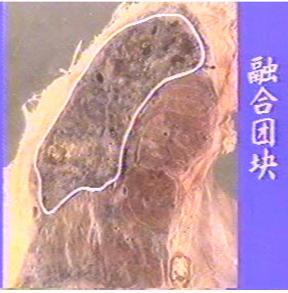

4.团块型矽肺:由上述类型矽肺进一步发展,病灶融合而成。矽结节增多、增大、融合,其间继发纤维化病变,融合扩展而形成团块状。该型多见于两肺上叶后段和下叶背段。肉眼观,病灶为黑或灰黑色,索条状,呈圆锥、梭状或不规则形,界限清晰,质地坚硬;切面可见原结节轮廓、索条状纤维束、薄壁空洞等病变。镜下除可观察到结节型、弥漫性间质纤维化型病变、大量胶原纤维增生及透明性变外,还可见被压神经、血管及所造成的营养不良性坏死,薄壁空洞及钙化病灶;萎缩的肺泡组织泡腔内充满尘细胞和粉尘,周围肺泡壁破裂呈代偿性肺气肿,贴近胸壁形成肺大泡;胸膜增厚,广泛粘连。病灶如被结核菌感染,形成矽肺结核病灶。

矽肺 矽肺

3)大阴影:在X射线胸片上,肺野内直径或宽度超过10mm的阴影,为晚期矽肺的重要X射线表现,形状有长条形、圆形、椭圆形、或不规则形,病理基础是团块状纤维化。大阴影的发展可由圆形小阴影增多、聚集,或不规则小阴影增粗、靠拢、重叠形成;多在两肺上区出现,逐渐融合成边缘较清楚、密度均匀一致的大阴影,常对称,形态多样,呈八字形等,也有先在一侧出现;大阴影周围一般有肺气肿带的X射线表现。